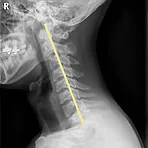

척추 교정 병원 다닌다 - 제1편 진단 접수 진료 척추 교정 병원 등록 해서 치료 받고 있다.여러가지 운동을 해봤는데 발레랑 스트릿까지 했는데 현상유지 정도 인것 같아서 병원에 가서 진단을 받아보기로 했다. 일단 골반은 정상인데 목, 등, 허리가 각도가 너무 안좋고 척추는 살짝 측만증이다.내 나이 31살이고 역대 몸이 가장 좋다고 생각했던 상황인데 실상은 무너지기 일보직전이었던것이지.그리고 가끔씩 허리가 아플때도 있어서 치료 받긴 해야 하겠다는 생각이 들었다.그리고 치료 받으면 좋아지겠다는 생각도 있었다.이게 내 사진은 아닌데 거의 내 사진하고 비슷해서 올려봄.목뼈가 위 짤처럼 1자로 되어있으면 저게 거북목이라고 한다.이게 정상 목뼈 사진. 이렇게 커브 형태가 정상이라고 한다.정확한 내 상태는 거북목이라..